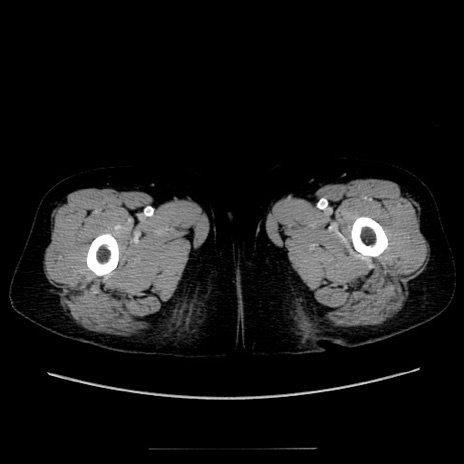

冠状断像

【症例】70歳代女性

【主訴】お腹が張る

【現病歴】1週間くらい前から腹部膨満の自覚あり。昨日夜から増悪したため、本日救急外来受診。

【身体所見】意識清明、BT 36.5℃、BP 165/106mmHg、HR 80bpm、SpO2 98%、腹部:膨満、軟、自発痛・圧痛なし、触診にて不快感あり、腸蠕動音:減弱

【データ】WBC 12600、CRP 1.04